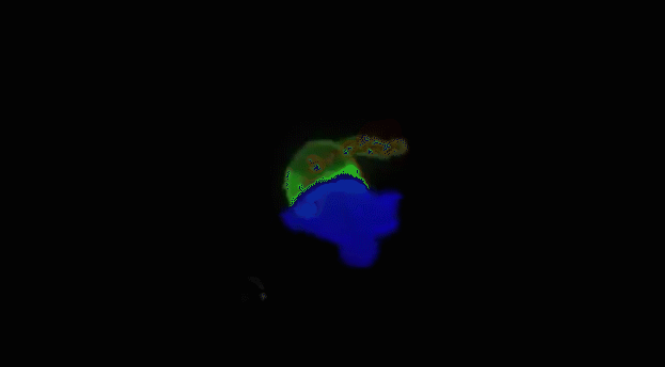

当T细胞(绿色)发现癌细胞时,通过分泌的毒素附着在癌细胞上,

来检测、分辨正常细胞与癌细胞

查明之后,T细胞(棕色)连接癌细胞,打破癌细胞外壁,

向其表面引入毒性蛋白,将其消灭